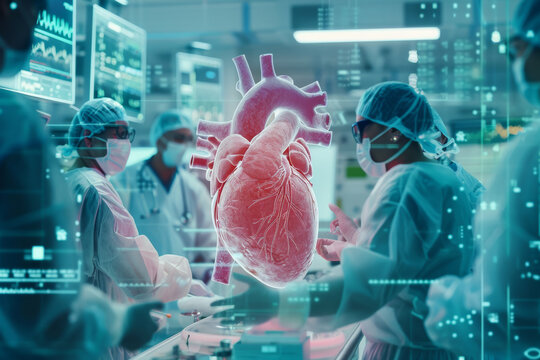

Heart health is one of the most crucial aspects of overall well-being. However, many people tend to ignore early warning signs, assuming them to be minor health issues. In reality, the body often gives signals when the heart is under stress. Early detection of these signs can have a significant impact in timely care and recovery. If you or a loved one experience persistent warning signs, seeking heart failure treatment in Surat could enhance quality of life and help avoid issues.

Heart failure doesn’t mean the heart has stopped working. Instead, it means the heart is not pumping blood as effectively as it should. This condition may progress gradually, and its symptoms can be subtle at the beginning. Identifying early signs and consulting a specialist in Surat for proper treatment is the best way to manage the condition.